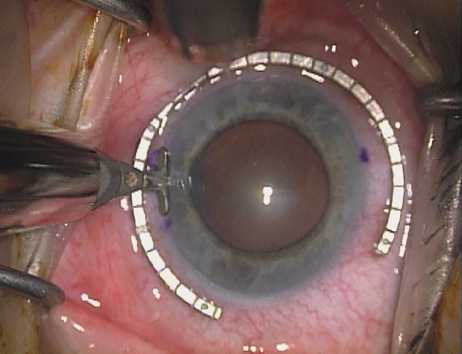

Case 1 is a 68-year-old male who presented for right cataract surgery. His refraction was −1.00 +2.25 × 80 and was recorded as reliable, consistent with his modest cataract density. Keratometry readings were 44.75 × 75 and 43.00 × 165. Corneal topography confirmed slightly more than 2.00 D of regular and slightly oblique cylinder. Consulting the nomogram, a plan was devised for a pair of LRIs to be centered over the 75-degree axis, with each incision delineating 45 degrees of arc. A single plane phaco incision was used and maintained at a size of less than 3.2 mm (Figs. 811).

Fig. 8. Steep meridian is confirmed intraoperatively by keratoscopy. In this left eye viewed from the temporal side, the “short axis” of the corneal mire is seen to be at the 75-degree meridian. (Reprinted from Hardten DR, Lindstrom RL, Davis EA. Phakic Intraocular Lenses: Principles and Practice. Thorofare, NJ: SLACK Incorporated, 2004, with permission.)

Fig. 9. The broad hash marks of the fixation ring/gauge are centered over the 75-degree meridian, using the 6:00 limbal mark for orientation. Alternatively, a Mendez gauge may be used. (Reprinted from Hardten DR, Lindstrom RL, Davis EA. Phakic Intraocular Lenses: Principles and Practice. Thorofare, NJ: SLACK Incorporated, 2004, with permission.)